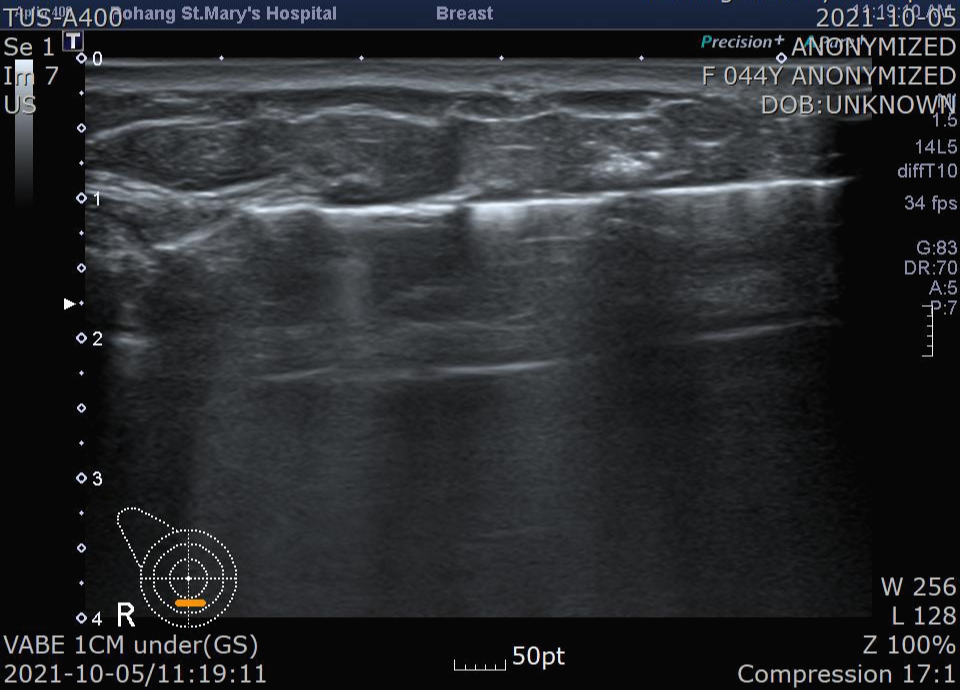

또 자릅니다.

또 열고,